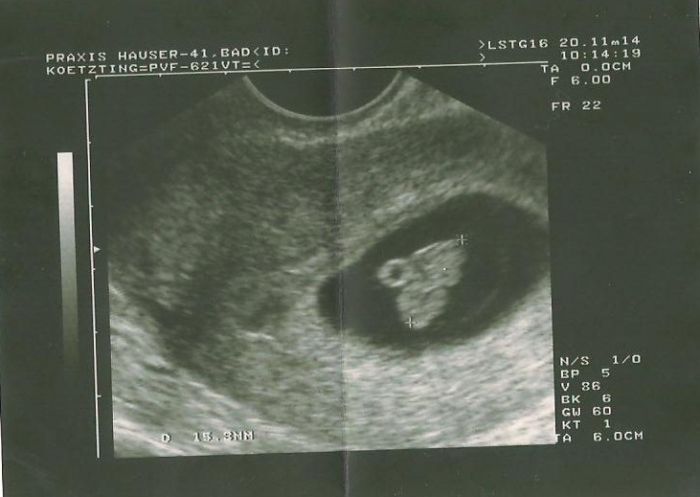

[673510] já měla posldní UZ 20.11. ten vaginální.. koukni na fotečku..